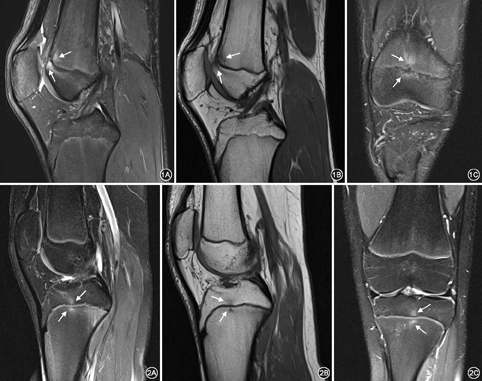

12例无外伤患者共有15个水肿区,9个位于股骨远端(图1),4个位于胫骨近端(图2),2个位于腓骨近端。MR表现为以骺板为中心的局限性线状或小斑片状T1WI低信号,PD-FS高信号区,病变波及邻近的骨骺和干骺端,而骨骺板未见异常。其中2个水肿区表现为骺板边缘线状水肿区,其余水肿区均为不同程度斑片状水肿。水肿范围(14.5±6.6)mm,其中水肿区域的范围3.9~7.9 mm的有3个,7.9~21.1 mm有10个,21.1~28.8 mm有2个(表1)。本组MR检查均未发现可以解释膝关节疼痛的异常征象,所有病例均经随访证实患者未进行任何治疗,膝关节疼痛逐渐减轻,最终疼痛完全消失,骺板区水肿范围缩小或消失。

外伤组16例,共有20个水肿区域,股骨骺板区水肿14个,胫骨骺板区水肿6个。其中19个水肿区MR表现为骺板区大小不等的片状T1WI低信号,PD-FS高信号,以PD-FS显示最佳(图3),仅1例患者骺板区水肿表现为线状T1WI低信号,PD-FS高信号。此外,4例患者MR显示骺板局部不规则变薄,PD-FS序列局部信号增高。水肿范围(26.2±8.8)mm,其中水肿区域的范围10.3~17.5 mm有2个,17.5~35.0 mm有15个,35.0~42.7 mm有3个。此外,16例外伤患者中,5例患者仅表现为片状骺板区水肿,范围较大,但有明确的外伤史。5例患者有明显的骨折征象,并经手术证实(图4)。5例骨骺板损伤。4例手术证实为半月板损伤。内侧副韧带损伤及交叉韧带各2例(表2)。

本研究中12例无外伤膝关节疼痛患者均行MR检查,结果显示,以骺板为中心,波及邻近骨骺与干骺端的线状及斑片状质子压脂序列呈高信号改变,范围较局限,平均范围为(14.5±6.6)mm,且骨骺板仍处于未闭合状态。这与Zbojniewicz等[3]报道的FOPE基本相符。Zbojniewicz等[3]认为无外伤性膝关节疼痛的青少年患者,其膝关节MR检查可以见FOPE,并经8个月以上的随访证实,FOPE很可能和生理性骺板闭合有关。本组12例15个水肿区,患者均无外伤史,但临床表现为膝关节疼痛,这可能与FOPE有关。因此,对青少年膝关节疼痛且无外伤的患者,MR检查发现FOPE区特征性的表现时,可能与生长痛或生理性骺板闭合有关,建议不要被误诊为异常,不需要进行侵袭性的检查。

外伤性骺板区水肿主要由于创伤使病变区骨髓受损出血、水肿以及骨小梁的断裂所致[9]。国内学者[10]通过研究儿童肘关节骨骺损伤发现,骺板周围1 cm范围内出现的骨髓水肿提示该处存在隐匿性骨折或者骨挫伤;本研究16例有明确的外伤史患者,骺板周围水肿均表现为T1WI序列呈片状低信号,PD-FS序列呈高信号改变,但水肿的范围较大,平均(26.2±8.8)mm。此外,外伤性骺板区水肿大多伴有骨折、肌腱韧带及半月板等结构损伤,如胫骨平台后外侧以及股骨外侧髁处的骨挫伤可以提示可能存在前交叉韧带的损伤[11,12]。因此,对于有明确外伤史,且MR检查表现骺板区片状水肿的患者,应警惕可能存在骺板及其周围结构的隐匿性损伤,以减少漏诊。

本研究结果表明,外伤性骨骺板区水肿范围明显大于非外伤性水肿,且以片状信号为主,水肿区最远端距离骺板较远,而非外伤性骺板周围区水肿范围小,水肿范围距离骺板较近。这一研究结果为两种骺板区水肿的鉴别诊断提供了新的影像学证据。